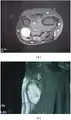

MRI showing schwannoma of ulna nerve -